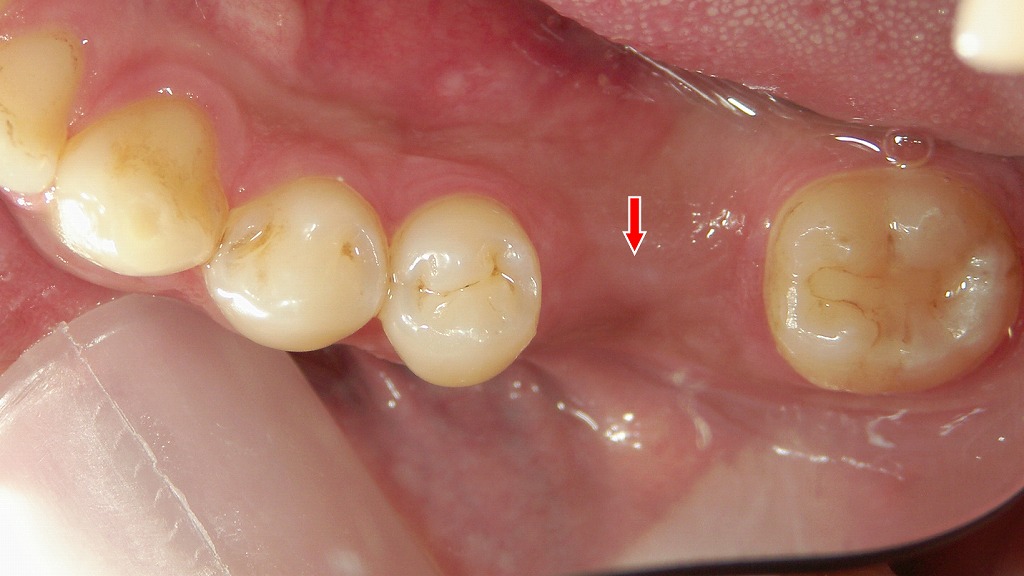

このデンタルX線画像では、赤い矢印で示された領域に上顎第一大臼歯(上顎6番)周囲の歯槽骨がほぼ完全に吸収している様子が確認できます。以下に詳しく説明します。

🦷 所見の概要

- 問題の歯:上顎第1大臼歯(6番)

- 歯根の周囲に広範な**X線透過像(黒い領域)**が認められます。

これは骨が失われている(吸収されている)ことを意味します。 - 周囲骨のパターンが消失しており、歯槽骨頂部から根尖部まで連続的に骨吸収が進行しています。

⚠️ 臨床的な注意点

- この骨吸収では、保存治療は困難であることが多いです。

抜歯を検討する段階に達している可能性があります。 - 周囲炎症が強い場合、上顎洞への波及も起こりうるため、CTによる精査が有効です。

- 隣接歯への影響(骨支持の減少や感染拡大)にも注意が必要です。

抜歯後の対応として行うインプラント治療の流れ ― 下顎6番欠損症例 ―

下顎6番を抜歯後、欠損部を放置せずインプラント治療を行った症例です。抜歯後の口腔内所見から、欠損相当部位へのインプラント埋入、さらに上部構造装着後のX線所見までを示しています。インプラントは隣在歯を削ることなく欠損部のみを補えるため、噛み合わせの維持や周囲歯への負担軽減につながります。機能性と長期的な安定性を重視した、抜歯後の有効な補綴治療の一例です。